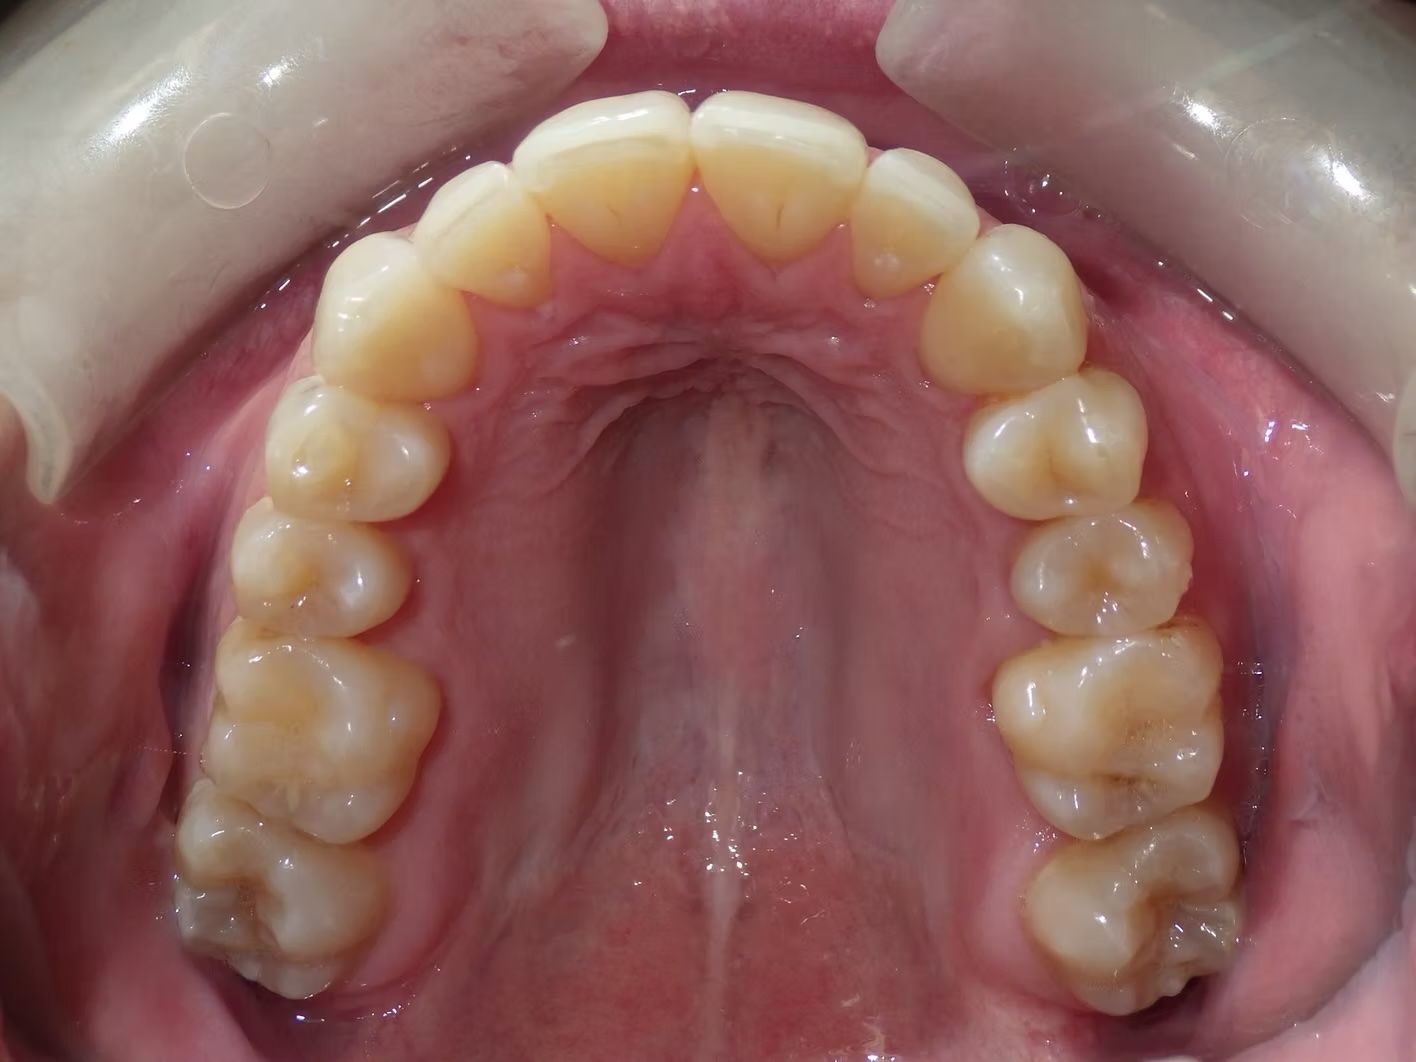

IAN

Ian came to the office because his lower teeth were crowded and he had an anterior cross bite. With traditional braces we resolved the crowding and aligned the teeth without causing flaring of the incisors and giving him a handsome smile. The treatment lasted 18 months and the final photos are at a 2 year follow up when we made him a new clear retainer.